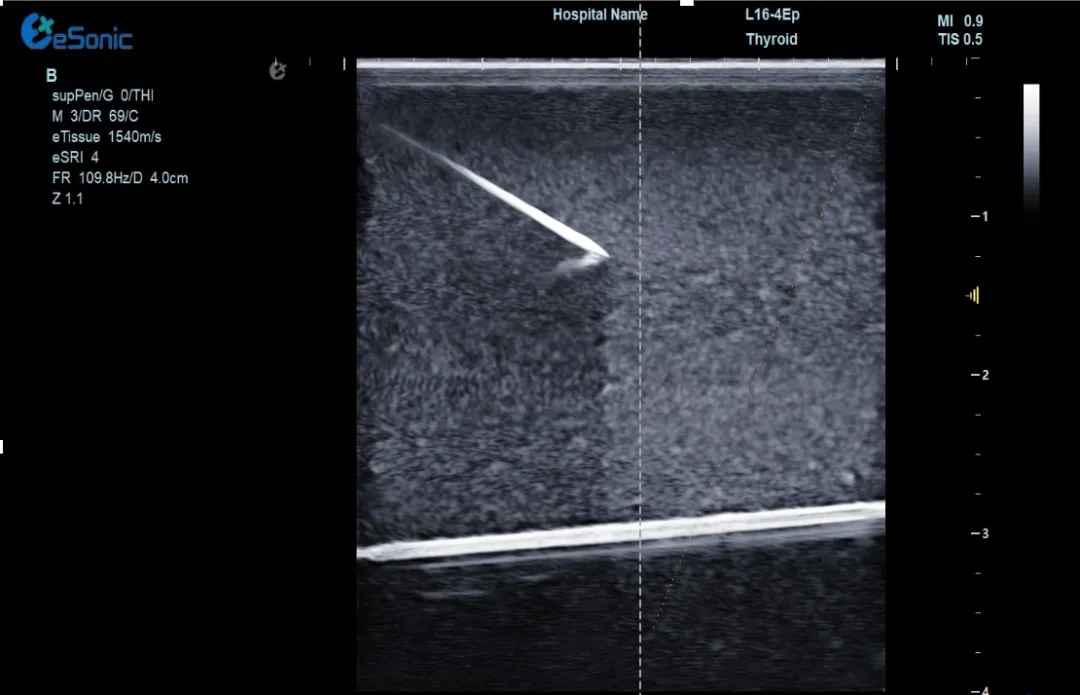

穿1.jpg

(1)实时追踪针尖:超声增强技术全程显示针尖位置,避免误伤血管、神经,穿刺成功率提升50%!

(2)动态路径预判:AI算法提前规划最佳穿刺路径,复杂位置的肝肿瘤、甲乳结节也能“一针到位”。可广泛应用于椎管穿刺或消融治疗等,使医生更易区分针尖和韧带等强回声,实时定位针尖位置,减低有创操作风险。